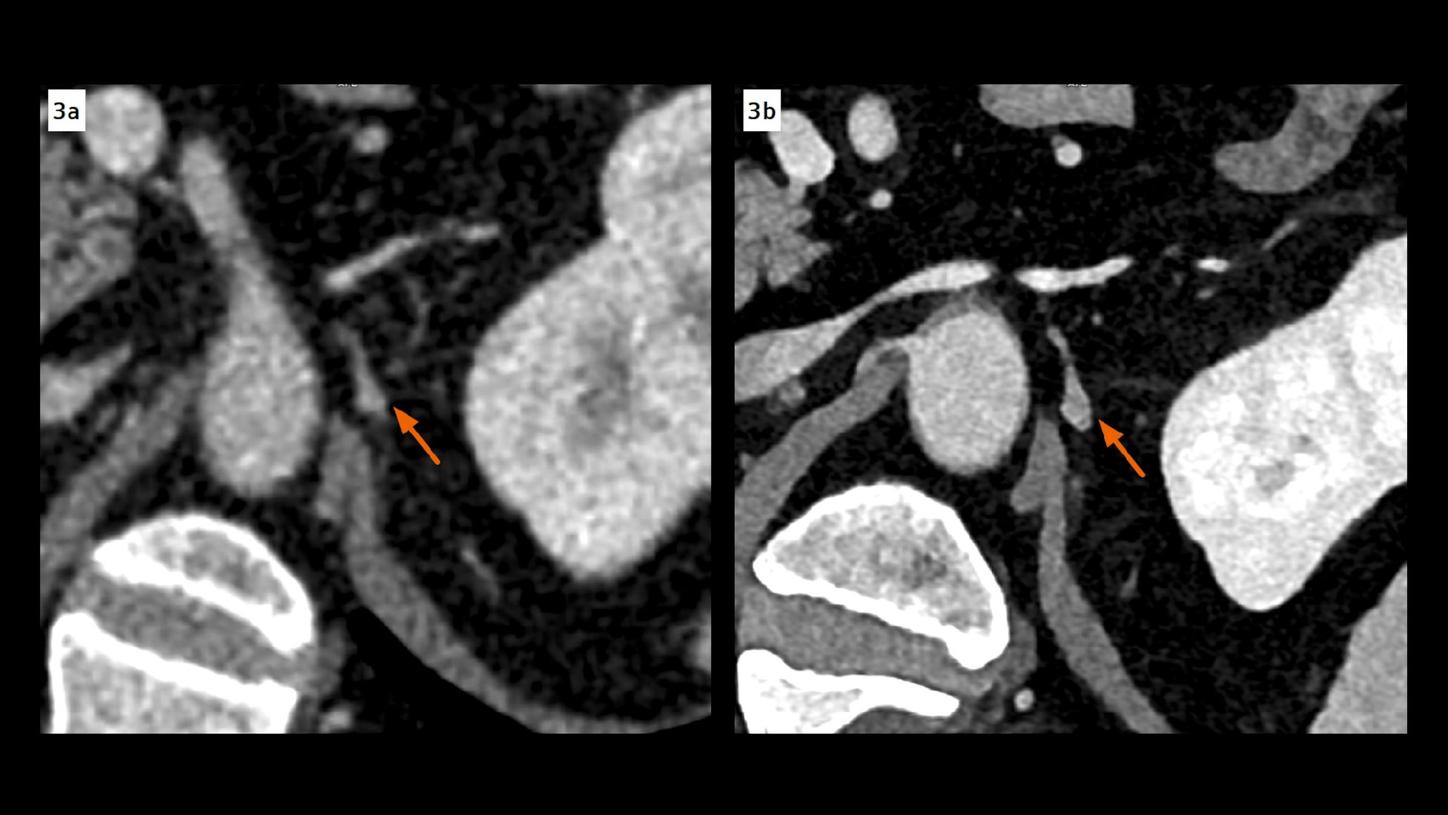

Fig. 3:Thickening and enhancement of the left celiac ganglion, not shown in an EID CT image (Fig. 3a, arrow, 1 mm), is clearly seen in a PCD CT image (Fig. 3b, arrow, 0.4 mm), indicating a metastasis. It is also confirmed by pathological analysis after surgery. Both images are displayed at same window settings. Note the improved contrast in the PCD CT image using a VMI displayed at 50 keV.